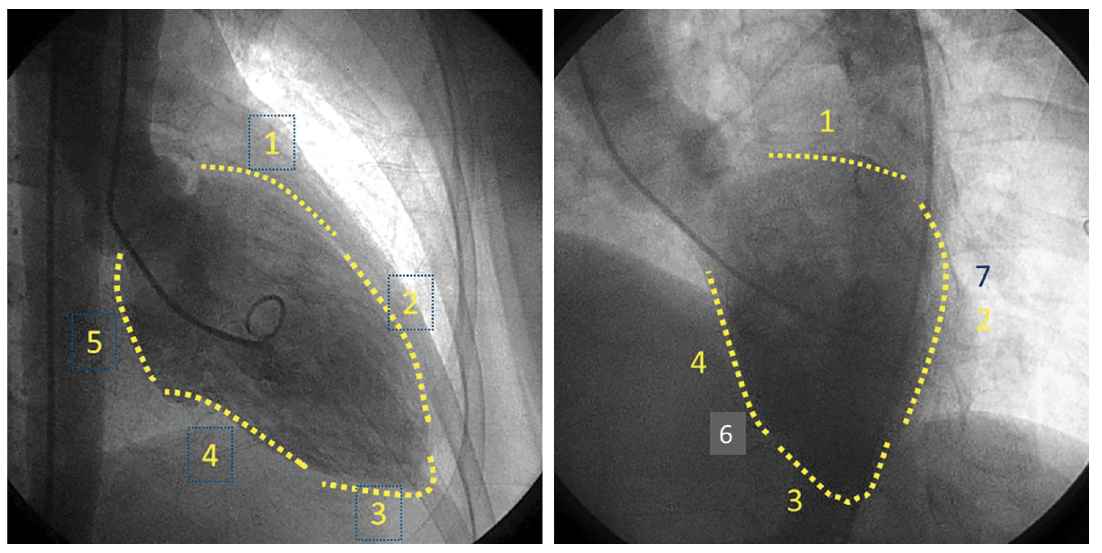

Contrast left ventriculography is still part of coronary angiography but information on left ventricular (LV) function comes from the echocardiogram. The LV end diastolic pressure (LVEDP) is also informative and easy to obtain after the angiogram. The LVEDP can be obtained with an end hole coronary catheter but only pigtail catheter should be used for ventriculography.6 Contrast ventriculography provides additional information about the ejection fraction, any mitral regurgitation, and LV wall motion abnormalities. Ventriculography is mostly performed in the RAO view. The septal and lateral LV walls can be visualized in the LAO view with cranial angulation (Figure 11).